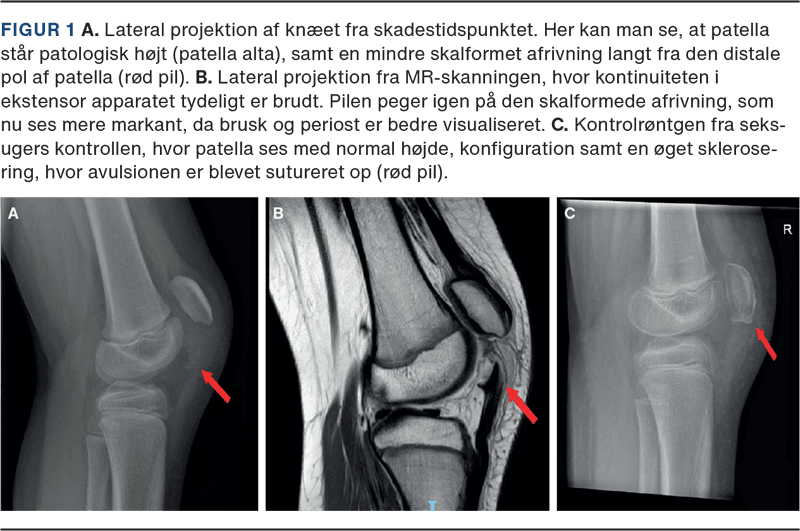

Efterfølgende blev der taget røntgenbilleder af knæet (Figur 1 A), hvor man ikke fandt tegn på frisk ossøs skade eller anden akut patologi. Patienten blev herefter hjemsendt med støtteforbinding. Ved vanlig gennemgang af røntgenbilleder, som blev varetaget af ortopædkirurgisk bagvagt og radiolog følgende dag, bemærkede man dog, at patella stod patologisk højt (patella alta), samt et diskret røntgenfast fragment distalt for patella. Dette foranledigede en akut MR-skanning (Figur 1 B), som her bekræftede mistanken om patella sleeve-fraktur.

Herefter fik patienten påmonteret en DonJoy-bandage over knæet, som gradvist blev låst op i bevægeudslag fra strakt til ulåst gennem de næste seks uger. I denne periode måtte patienten fuldt vægtbære, og der blev løbende gjort kliniske og radiologiske kontroller. Ved den afsluttende seks- ugers kontrol var patienten uden smerter, kunne frit gå og ekstendere ubesværet. Ligeledes kunne man se, hvordan patella stod anatomisk korrekt på røntgenbilledet (Figur 1 C).